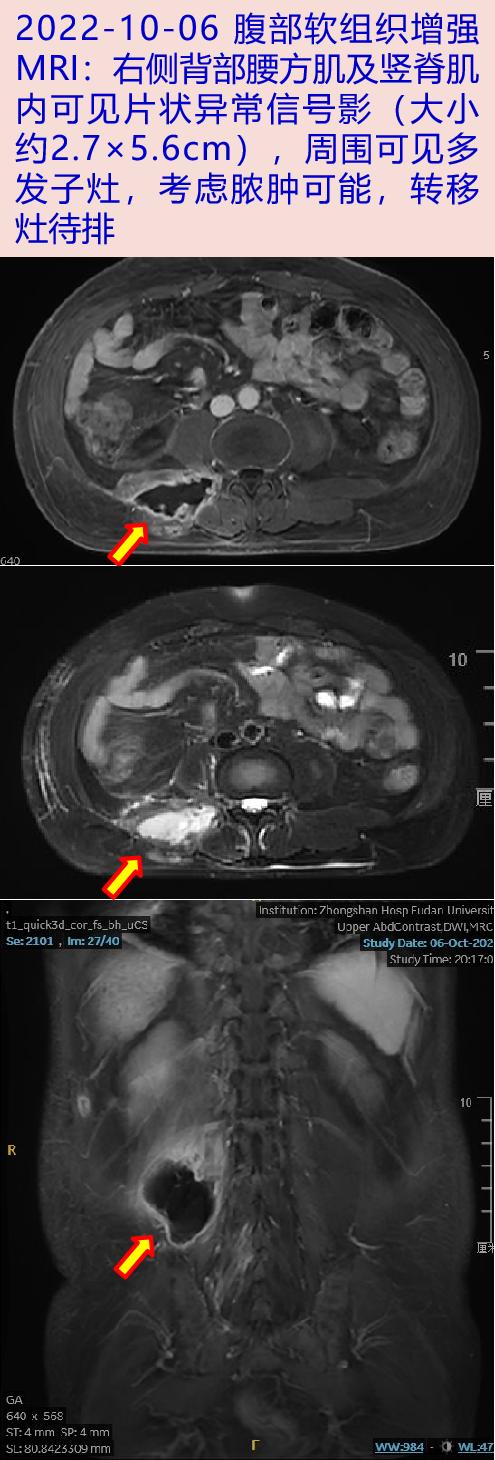

2022-10-06 行上腹部增强MRI:肝右叶多发HCC伴门静脉癌栓;肝硬化伴硬化结节;门脉高压,脾大。腹部软组织增强MRI:右侧背部多发病灶,脓肿可能,转移灶待排。10-08加用左氧氟沙星0.5g qd,后腰痛较前好转,体温平,10-12为明确背部病灶性质收入中山医院感染科。

2022-11-11 我院随访,腰痛完全缓解,体温平。复查腹部软组织增强MRI:右侧腰背部脓肿较前2022-10-06明显好转,予拔除引流管。继续左氧氟沙星抗感染,门诊随访。